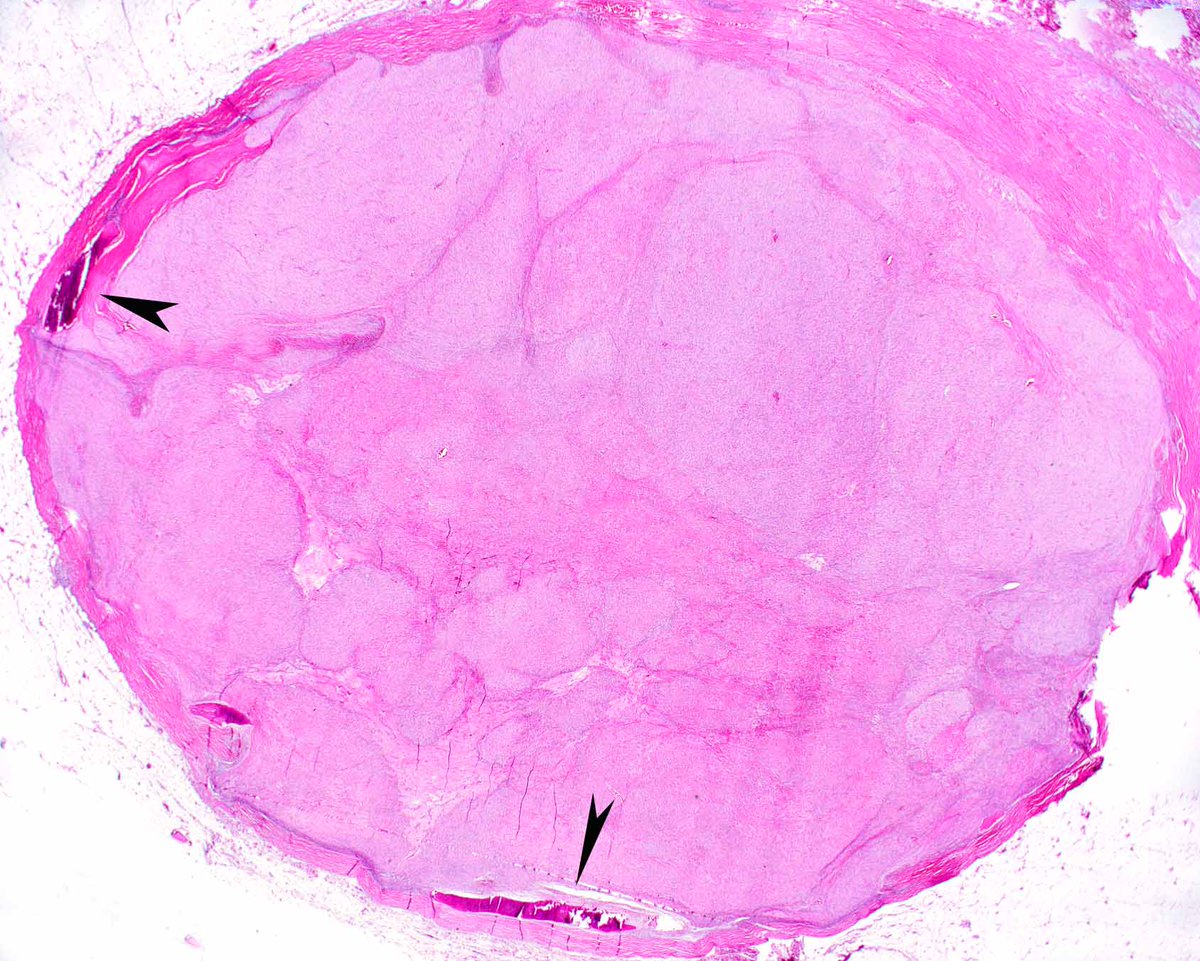

This classic example of ossifying fibromyxoid tumor displays a shell of bone and uniform cytologic features; it's an H&E diagnosis. Without classic features, detecting PFH1 rearrangements (several partner genes reported) is useful. #UMiamiPath PMIDs: PMID: 2476942, 23887158.